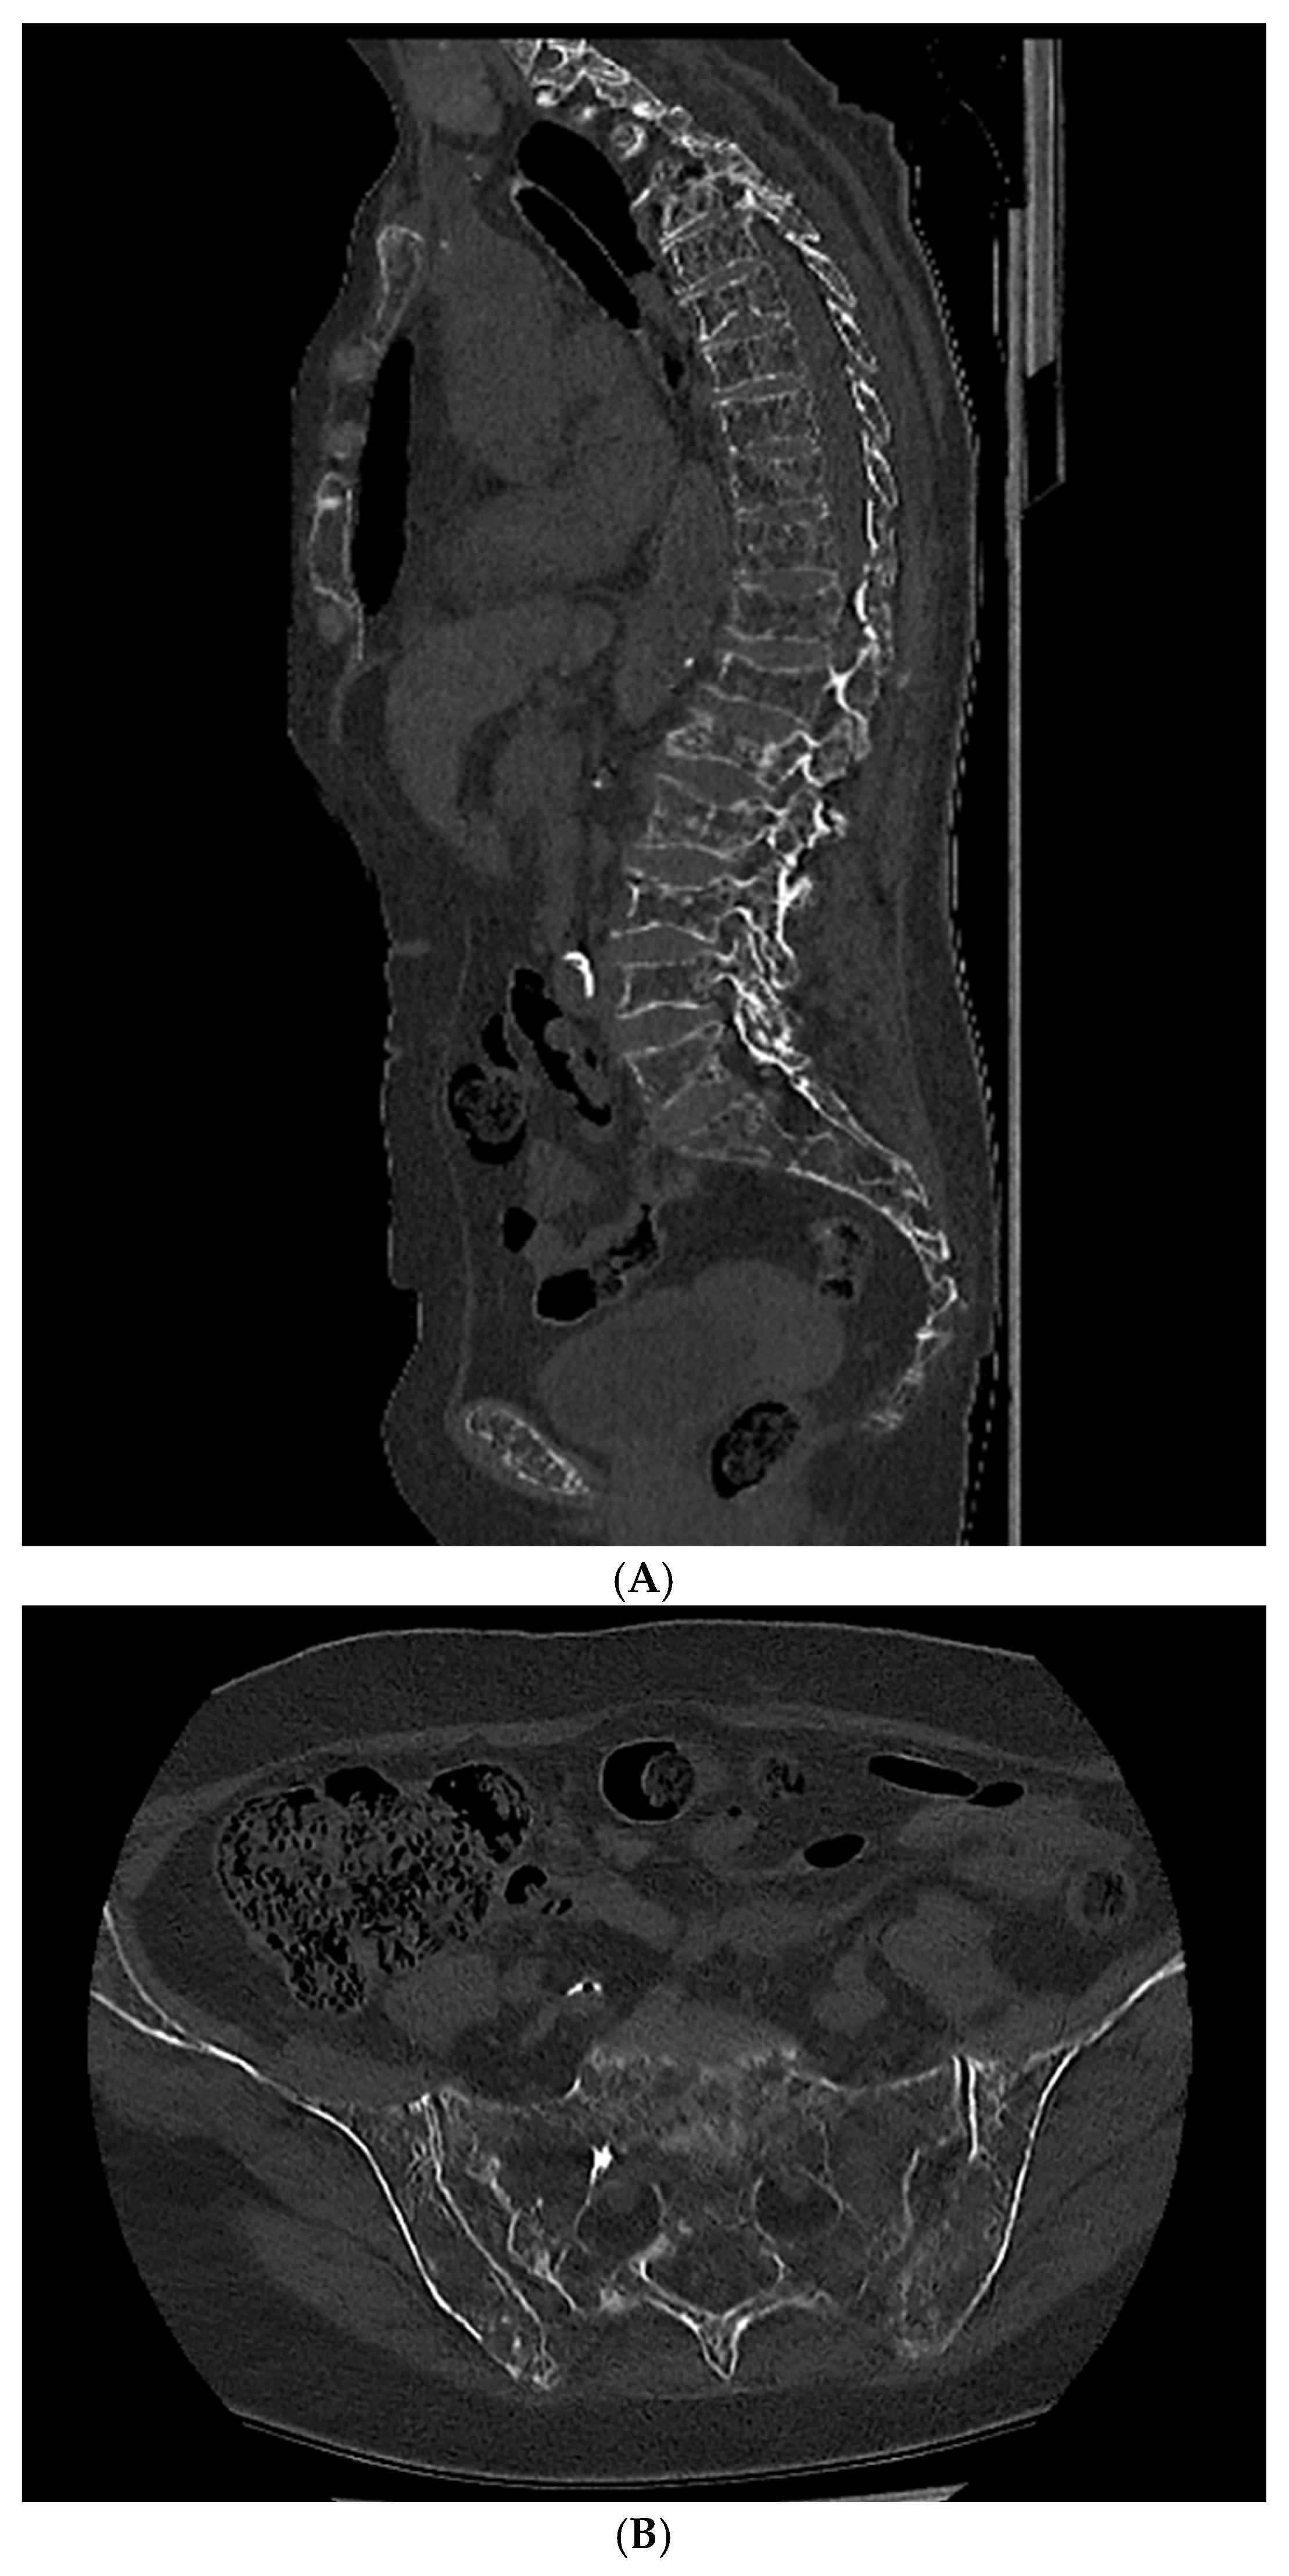

The presence of one or more sites of osteolytic bone destruction, at least 5 mm or greater in size, fulfills the criteria of bone disease in MM (CRAB), and therefore makes it necessary to initiate treatment (Figure 1, Figure 2 and Figure 3). In the case of smaller suspicious lesions seen in WBLDCT, they should be imaged within 3–6 months with CT or MRI to avoid overinterpretation [21,22].

Figure 1. A 77-year-old woman with a diagnosis of multiple myeloma. (A)—Whole-body low-dose computed tomography demonstrates lytic lesions in (A) vertebral bodies and (B) sacral bone and iliac crest. Source: Radiological Diagnostics Center, The National Institute of Medicine of the Ministry of Interior and Administration, Warsaw, Poland.